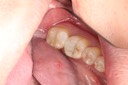

Chris Woo #14 pre-op

Chris Woo #14 caries removal

Chris Woo #14 prep